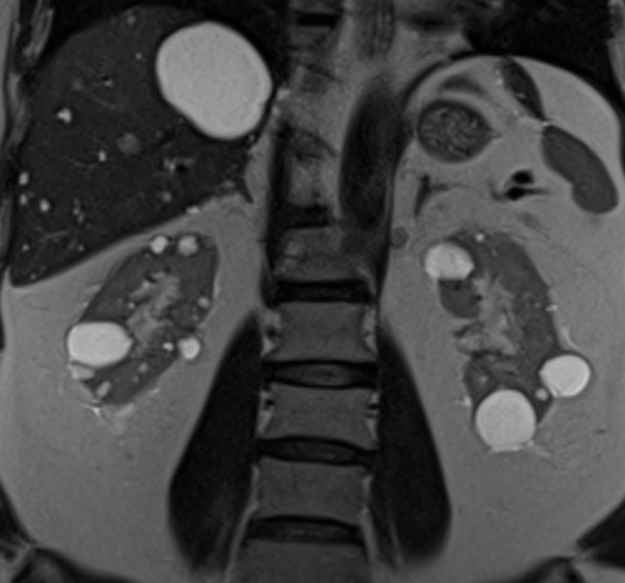

Simple and complex kidney cysts

Kidney cysts result from genetic or non-genetic processes. It can occur and affect children and in adults. It is usually diagnosed when a person goes for an ultrasound scan, CT scan or MRI scan of the abdomen. Kidney cysts can be divided to simple kidney cysts or complex kidney cysts. There is another condition where the kidney is filled with multiple kidney cysts which will be covered under cystic kidney disease.

The most common cause of these cysts are radiologically evident kidney cysts in adults are simple kidney cysts.